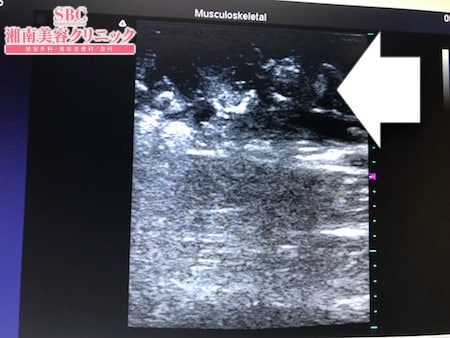

No.252802【脂肪吸引】もともとセルライトが気になっていたので脂肪吸引で解消する!左ふくらはぎ術中タッチビュー

今回はふくらはぎの脂肪吸引を行いましたので

その術中変化を紹介しましょう。

脂肪吸引はセルライトごと

体外に除去します。